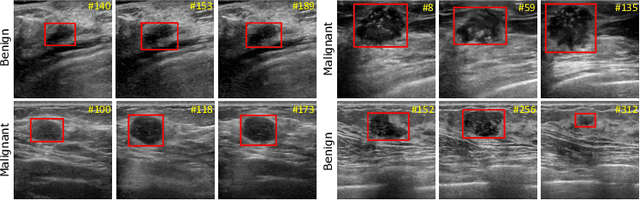

Abstract:Breast lesion detection in ultrasound is critical for breast cancer diagnosis. Existing methods mainly rely on individual 2D ultrasound images or combine unlabeled video and labeled 2D images to train models for breast lesion detection. In this paper, we first collect and annotate an ultrasound video dataset (188 videos) for breast lesion detection. Moreover, we propose a clip-level and video-level feature aggregated network (CVA-Net) for addressing breast lesion detection in ultrasound videos by aggregating video-level lesion classification features and clip-level temporal features. The clip-level temporal features encode local temporal information of ordered video frames and global temporal information of shuffled video frames. In our CVA-Net, an inter-video fusion module is devised to fuse local features from original video frames and global features from shuffled video frames, and an intra-video fusion module is devised to learn the temporal information among adjacent video frames. Moreover, we learn video-level features to classify the breast lesions of the original video as benign or malignant lesions to further enhance the final breast lesion detection performance in ultrasound videos. Experimental results on our annotated dataset demonstrate that our CVA-Net clearly outperforms state-of-the-art methods. The corresponding code and dataset are publicly available at \url{https://github.com/jhl-Det/CVA-Net}.